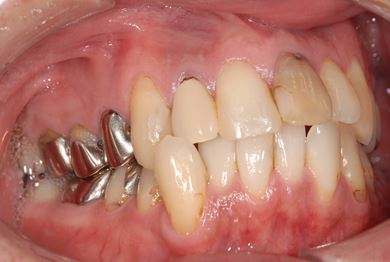

治療前

• 治療前